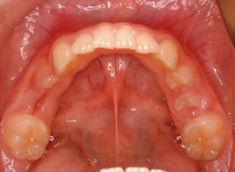

治療前

治療後(12ヶ月後)

上顎の劣成長が顕著なので、上顎犬歯の萌出するスペースが不足しています。

また、統計通り、左上の犬歯です。